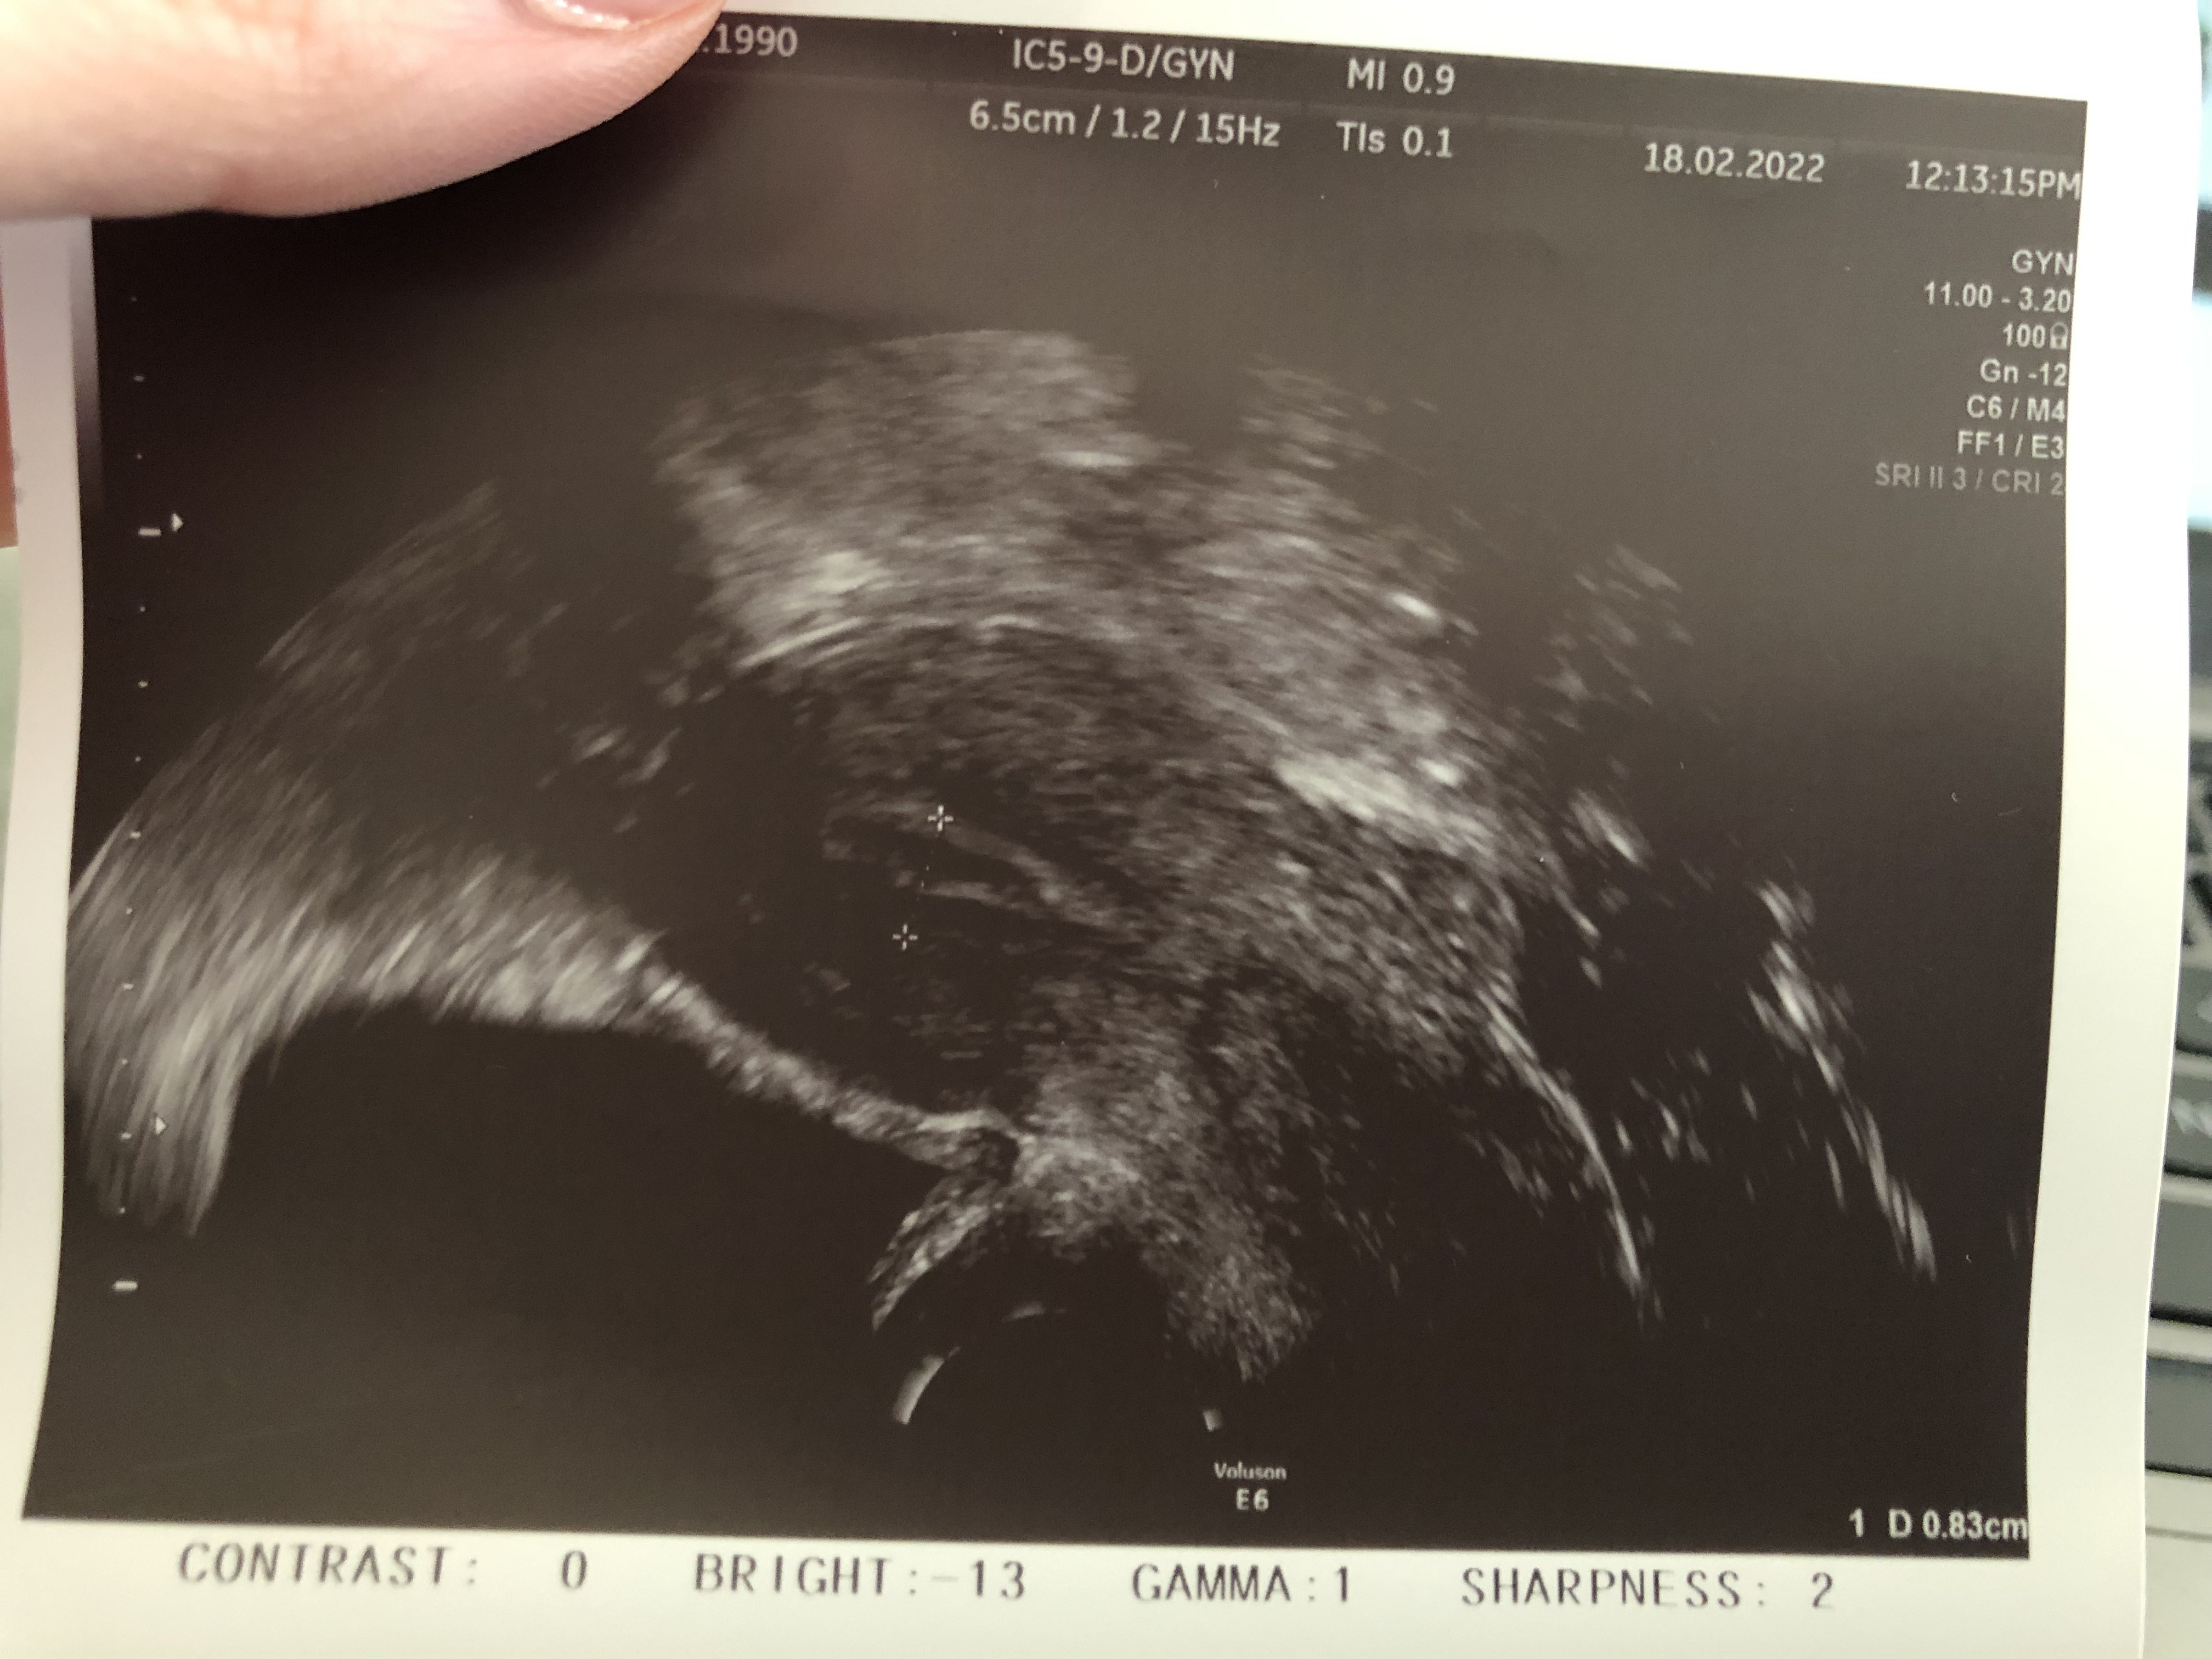

Dzisiaj 15dc, wieczorem były seksy i czop ze śluzu 🙈

Zastanawiałam się czy to zwiastun przed czy po owu bo bólu nie czułam i właśnie wróciłam z monitoringu, dziad nie pękł jeszcze - ma 23 mm i pan dr powiedział ze jest na granicy pęknięcia i działać wiec napisałam do starego żeby wracał do domu na HO 😂

Wstawiam Wam zdjęcie mojego wielkoluda 😂 i śluzówki